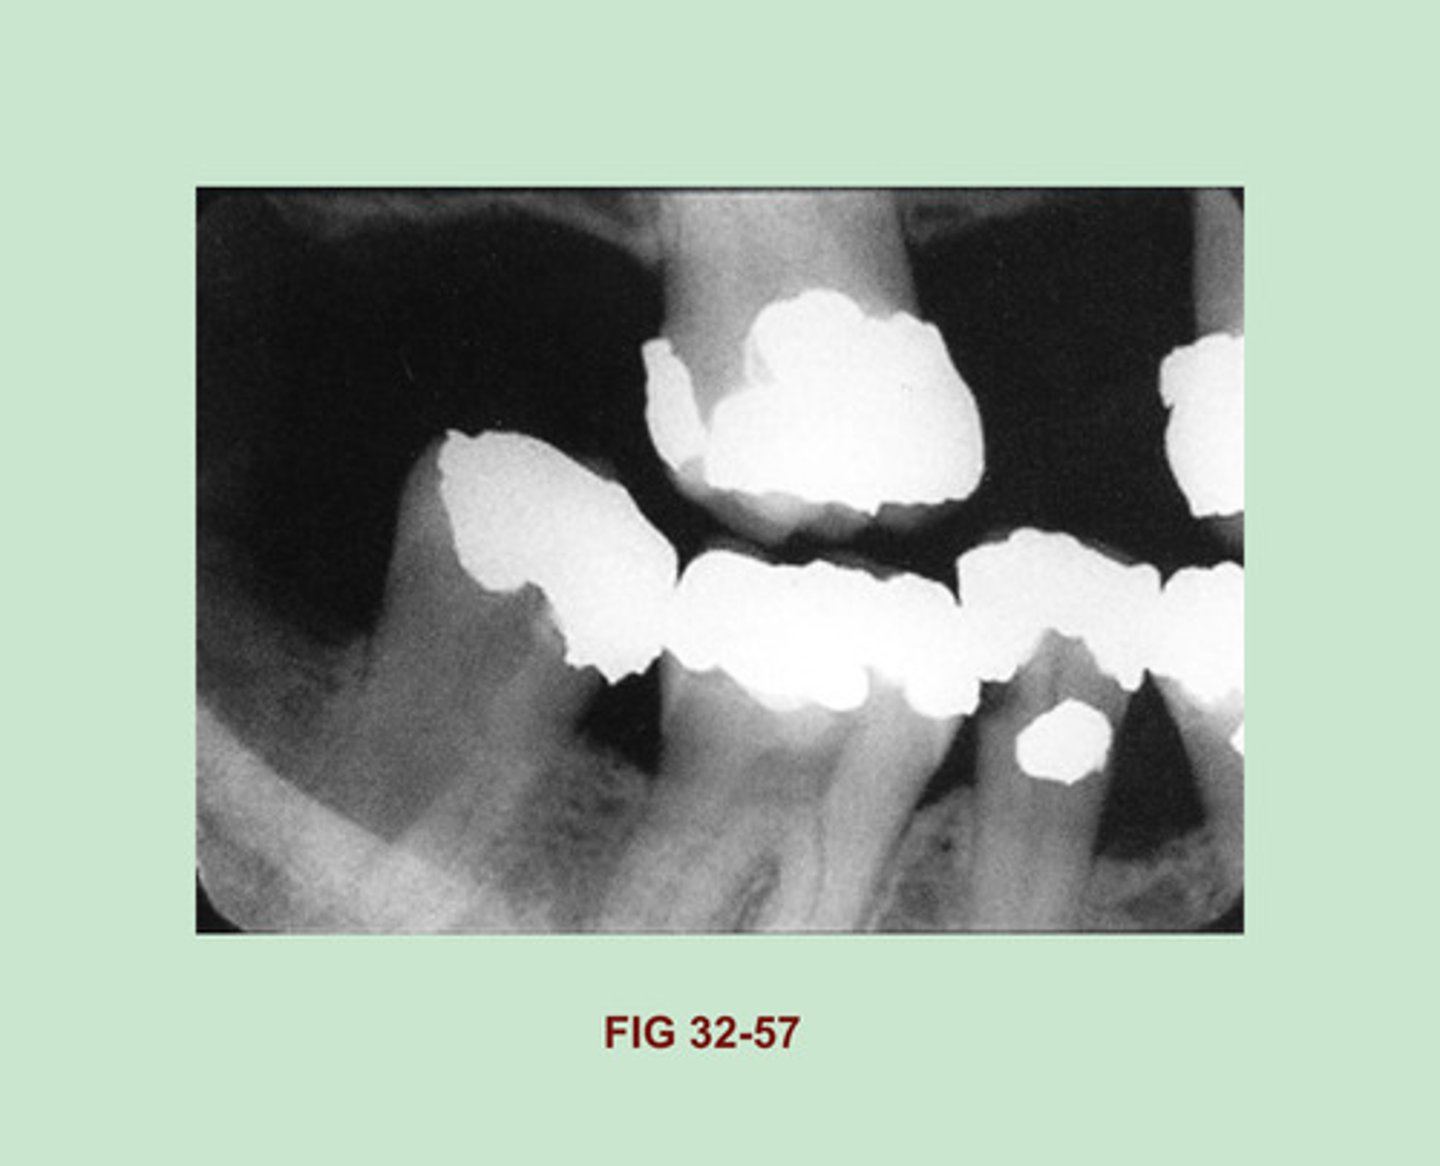

Identify the RESTORATIVE material seen in each tooth of this dental image (Figure 32-57).

Gold Foil Restorations

Side Note: One-surface gold foil restorations appear as small round radiopacities on a dental image and are indistinguishable from one-surface amalgam restorations. A two-surface gold foil restoration may appear similar to a gold inlay, with smooth, regular marginal outlines, or may exhibit slightly irregular margins & resemble a two-surface amalgam.